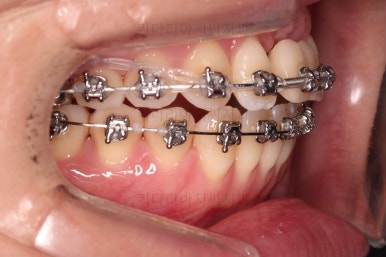

개방교합도 많이 다물어졌고, 2급 부정교합도 매우 많이 개선되었네요.

임플란트 가능 시점이 점점 다가오는데요.

임플란트를 한 번 하게되면 많은 치아 움직임은 없어야 되기 때문에, 앞니의 높이, 입매, 교합 등등 모든 점에서 평가가 진행됩니다.

임플란트 머리 부분이 올라가기까지 기다리는 동안 좀 더 부산개방교합 디테일을 맞추고 마무리를 합니다.